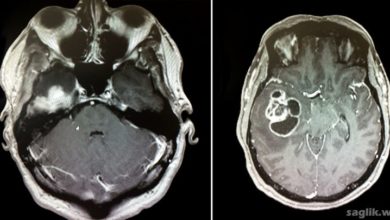

Glioblastoma Nedir? Glioblastoma Belirtileri, Nedenleri, Tedavisi

Glioblastoma (GBM), en sık görülen malign primer beyin tümörüdür. Glioblastoma ayrıca glioblastoma multiforme ve astrositom grade 4 olarak da adlandırılır.…